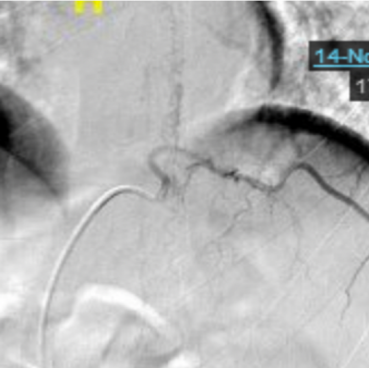

头颅MRA:椎动脉(R-VA)、基底动脉(BA)、右大脑中动脉(R-MCA)、右大脑后动脉(R-PCA)多发节段性重度狭窄(图4)。

图4 头颅MRA

第一阶段病程:患者亚急性起病,病初为双下肢无力,3个月期间无明显变化,3个月后突然急性加重,不符合急性脊髓炎的病程特点,结合下胸段脊髓长节段长T2信号、水肿明显、脊髓可见可疑的血管流空影,需考虑脊髓血管病。进一步完善颈胸腰椎增强MRI,可见胸髓多发斑片状异常信号、脊膜不均匀增厚伴强化、脊髓周围多发迂曲血管影、脊髓表面含铁血黄素沉积(图6)。脊髓数字减影血管造影(DSA)可见左侧T10肋间动脉造影时早期静脉充盈、迂曲扩张,考虑为硬脊膜动静脉瘘(SDAVF)可能大(图7)。治疗方面,于神经外科行硬脊膜动静脉瘘切除术。

图7 脊髓DSA

第二阶段病程:大剂量激素冲击治疗后出现发热、头痛、精神行为异常,腰穿脑脊液白细胞明显升高,考虑免疫抑制后继发感染性脑膜脑炎。脑脊液宏基因组学二代测序VZV序列数高,经抗病毒治疗后颅压、白细胞、蛋白及VZV序列数均明显下降,支持中枢神经系统VZV感染。此外,患者脑脊液蛋白显著升高,糖、氯化物降低,血结核感染特异性T细胞检测阳性,影像上脊膜增厚明显,需考虑合并中枢神经系统结核感染不除外。患者多发性脑梗死、局部蛛网膜下腔出血,颅内动脉多发节段性中重度狭窄,需考虑合并感染性血管炎可能。治疗方面,予以足量、足疗程抗病毒治疗及抗结核治疗。